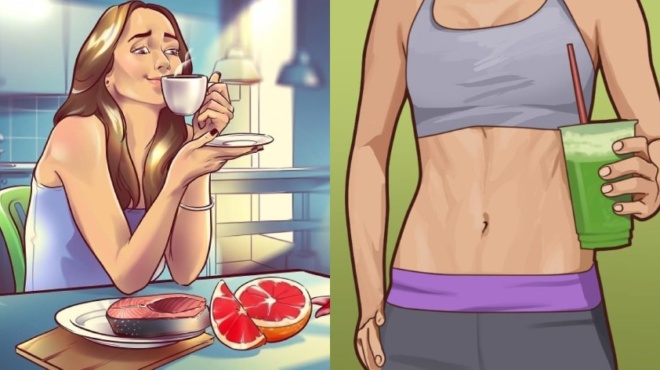

Εκτός από την άσκηση και την ηρεμία, αυτή που μπορεί πραγματικά να σας σώσει, είναι η διατροφή. Θαλασσινά που να έχουν υψηλά επίπεδα Ω-3 λιπαρών (σ.σ. σολομός, τόνος, κολιός). Σαλάτες και Smoothies, γεμάτες με αντιοξειδωτικές και αντιφλεγμονώδης ουσίες. Μπαχαρικά, όπως ο κουρκουμάς που είναι αντιφλεγμονώδης και έχει αντικαρκινικές ιδιότητες. Επίσης, η κανέλα, το τζίντζερ και η ουσία capsaicin, έχουν αντιφλεγμονώδεις ιδιότητες, χρήσιμες για τον οργανισμό.